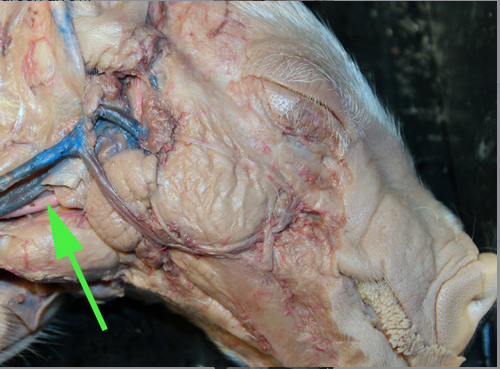

The vein marked by the green arrow is the

external jugular vein.